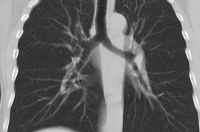

Продолжение сегодняшней истории про госпитализацию родителей журналистки Наталии Фурман: ее предположительно больная коронавирусом мать с постоянным кашлем должна пойти сдавать тест в больницу, рассказывает женщина.

- Спасибо всем, кто откликнулся на мой отчаянный пост. Представители здравоохранения оперативно связались с нами, подробно объяснили маме алгоритм дальнейших действий. Самое главное - возможность КТ предоставлена! Берегите себя и своих близких! - приводит слова Наталии "Секунда".